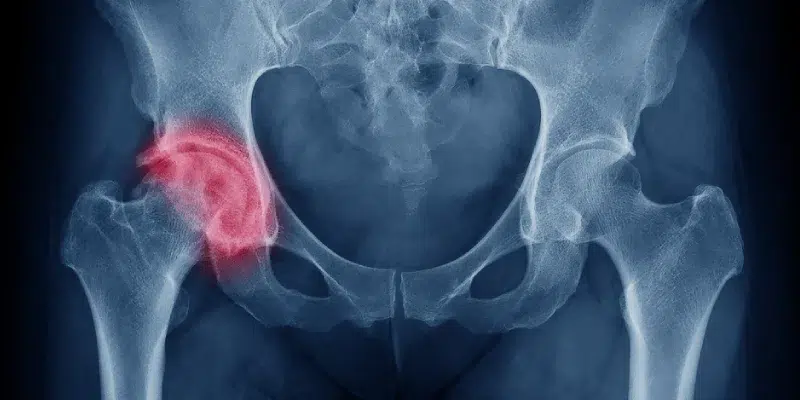

La necrosis avascular (también llamada osteonecrosis) es una condición en la que se interrumpe el flujo sanguíneo hacia el hueso, provocando la muerte del tejido óseo. A medida que la enfermedad progresa, el hueso puede debilitarse, colapsar y afectar la función articular, generando dolor intenso y limitación del movimiento.

Esta condición suele afectar la cabeza del fémur, aunque también puede desarrollarse en otros huesos como la rodilla, el hombro, la muñeca o el tobillo. Puede tener diversas causas, desde traumatismos hasta enfermedades metabólicas que afectan la circulación sanguínea.

¿Qué es la necrosis avascular?

El hueso, al igual que otros tejidos, necesita un suministro constante de sangre para mantenerse saludable. Cuando la irrigación sanguínea se interrumpe por un traumatismo o una enfermedad, las células óseas mueren y el hueso pierde su capacidad de regeneración.

Si no se trata a tiempo, puede causar colapso óseo y daño articular severo, lo que lleva a la pérdida de movilidad y a la necesidad de cirugía reconstructiva.

Diagnóstico de la necrosis avascular

• Radiografía: Detecta daños en etapas avanzadas.